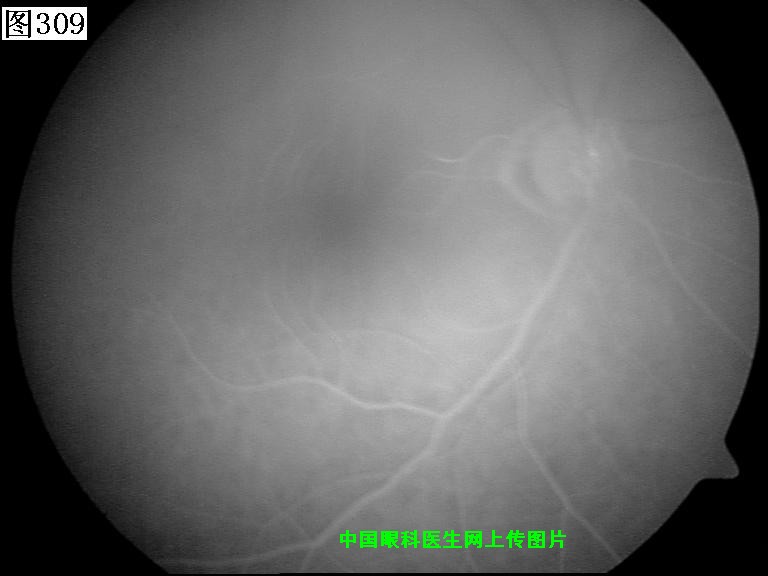

309 310 311 312